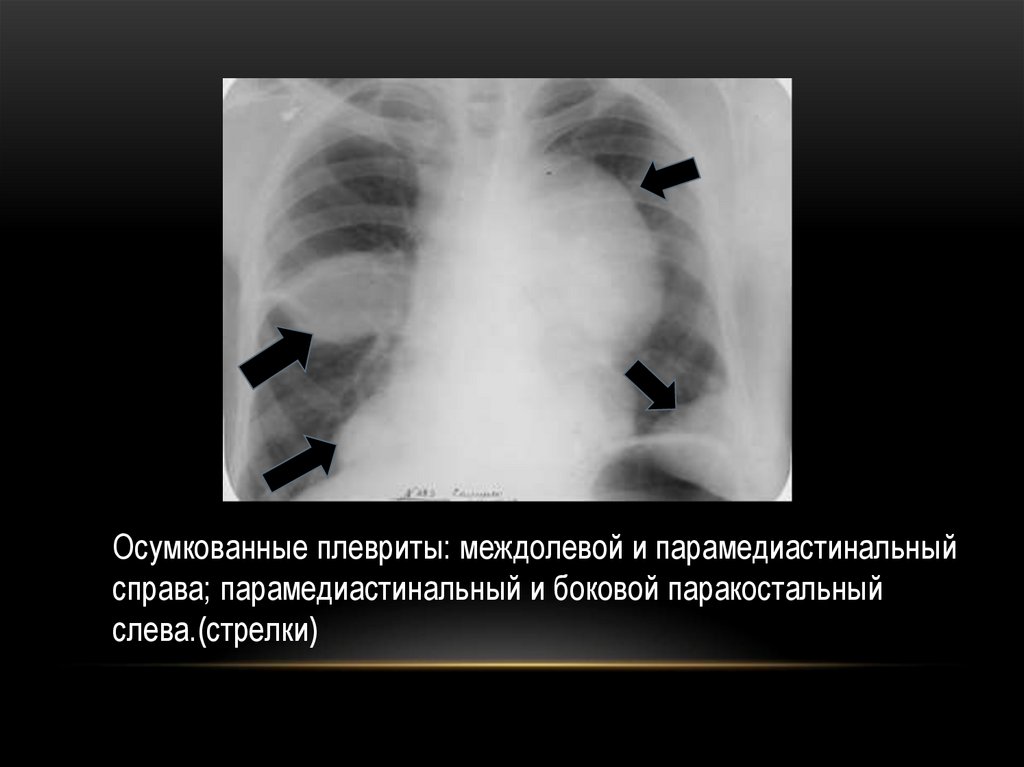

Осумкованные плевриты: междолевой и парамедиастинальный

справа; парамедиастинальный и боковой паракостальный

слева.(стрелки)